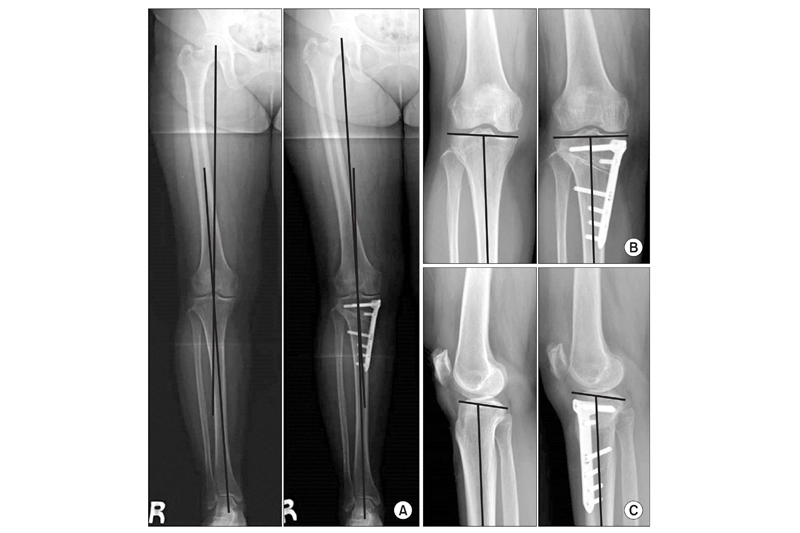

膝關節退化治療|手術糾正關節受力角度

高位脛骨截骨術的原理是,於小腿脛骨上方切開缺口後,將脛骨微曲及固定後,按力學原則將膝關節的受力角度轉向往外側,以減輕內側受力引起的痛楚,保護內側已有損磨的軟骨,當中會植入物料作固定及輔助脛骨復原。由於手術複雜度較低,約歷時1至2小時即可完成。患者於術後4至6星期已可復康,得以減少疼痛及減慢關節磨蝕,手術效果大約維持10年。楊仕俊醫生解釋,由於高位脛骨截骨術只可改變膝關節受力情況,對整體膝結構沒有改變,所以要挑選勞損未算太差的患者。

(圖片來自Offical Journal of Korean Knee Society)